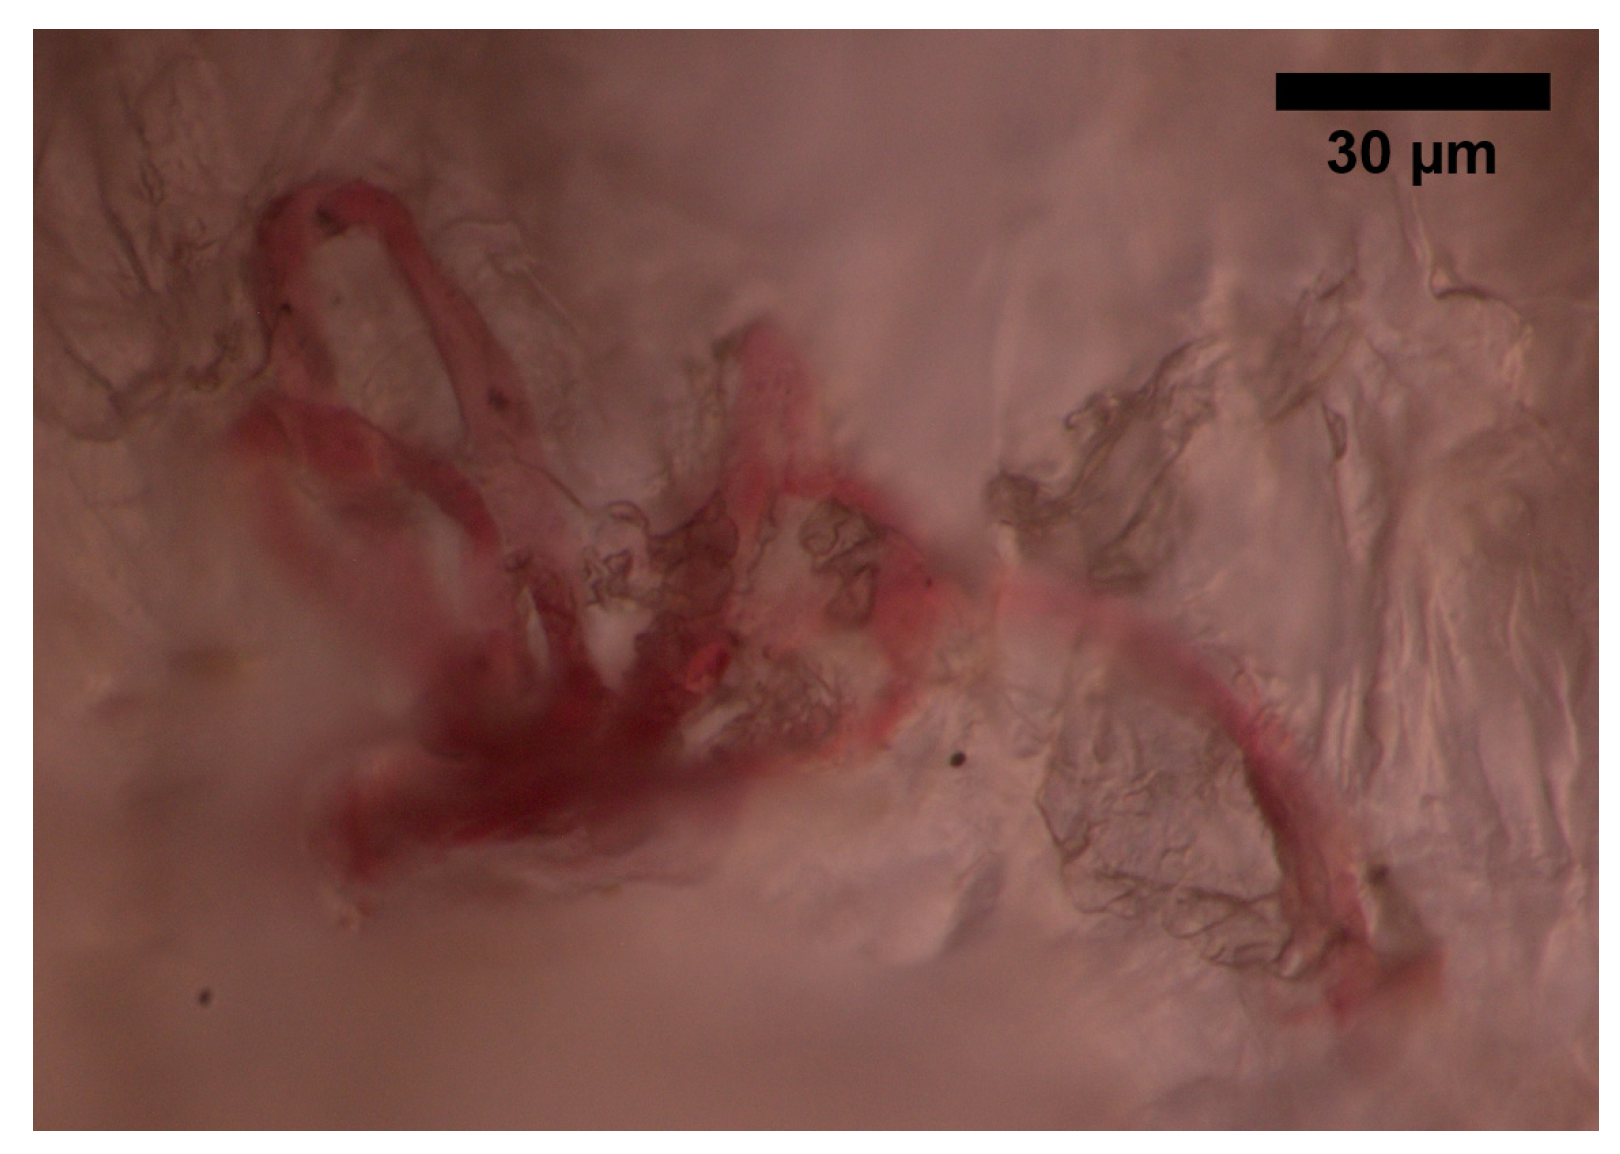

The superficial vascular plexus, which is a network of blood vessels located at the uppermost level of the dermis. From a histological point of view, this plexus marks the junction between the papillary and reticular dermis. The superficial plexus is composed of anastomosing small-calibre arterioles that branch off into capillaries, which extend into dermal papillae to supply the boundaries between the epidermis and dermis and envelop adnexal structures [25]. Each dermal papilla is provided with at least one capillary loop [24]. In Figure 2, an image of a pig skin sample—obtained through a 50× microscope objective and a lateral scan at different depths—shows an example of a capillary loop.

Figure 2. Image of a capillary loop from a sample of pig skin obtained with an optical microscope and an M-Plan APO 50 × 0.55 NA microscope objective.